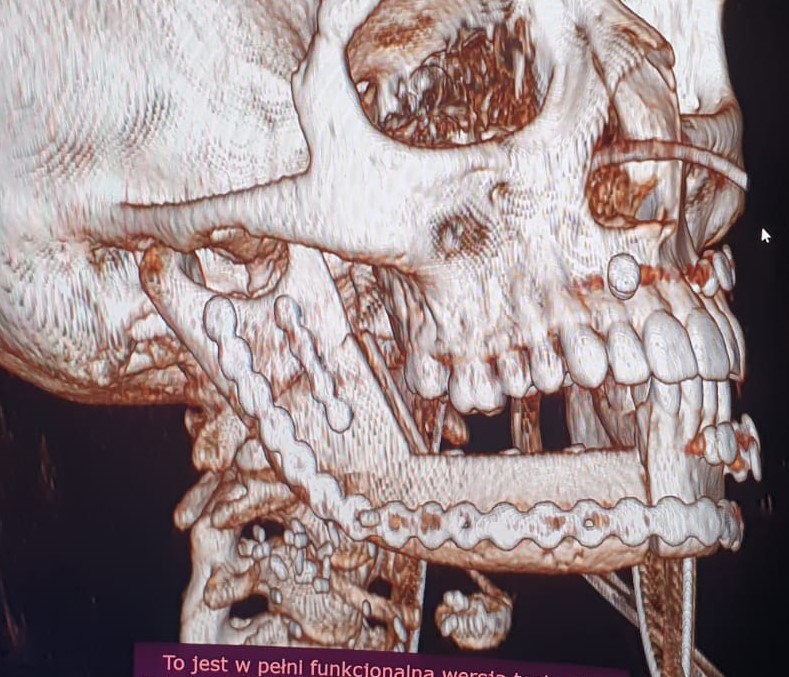

W okresie pooperacyjnym nie stwierdzono powikłań w gojeniu ran pooperacynych. W wykonanych badaniach tomografii komputerowej części twarzowej czaszki (Fig. 21.) oraz OPG (Fig. 22.) potwierdzono poprawność rekonstrukcji żuchwy oraz prawidłową pozycję jednoczasowo założonych implantów. Po upływie 6 miesięcy od wykonanego zabiegu chirurgicznego i pełnym zrośnięciem się kikutów żuchwy z płatem mikrochirurgicznym z talerza kości biodrowej oraz osteointegracji implantów zębowych z przenoszonym fragmentem kostnym w chorej planowane są dalsze etapy leczenia implantoprotetycznego.

Fig. 21. Odtworzony fragment trzonu, kąta i gałęzi żuchwy po stronie prawej na rekonstrukcjach 3D kontrolnego badania tomografii komputerowej